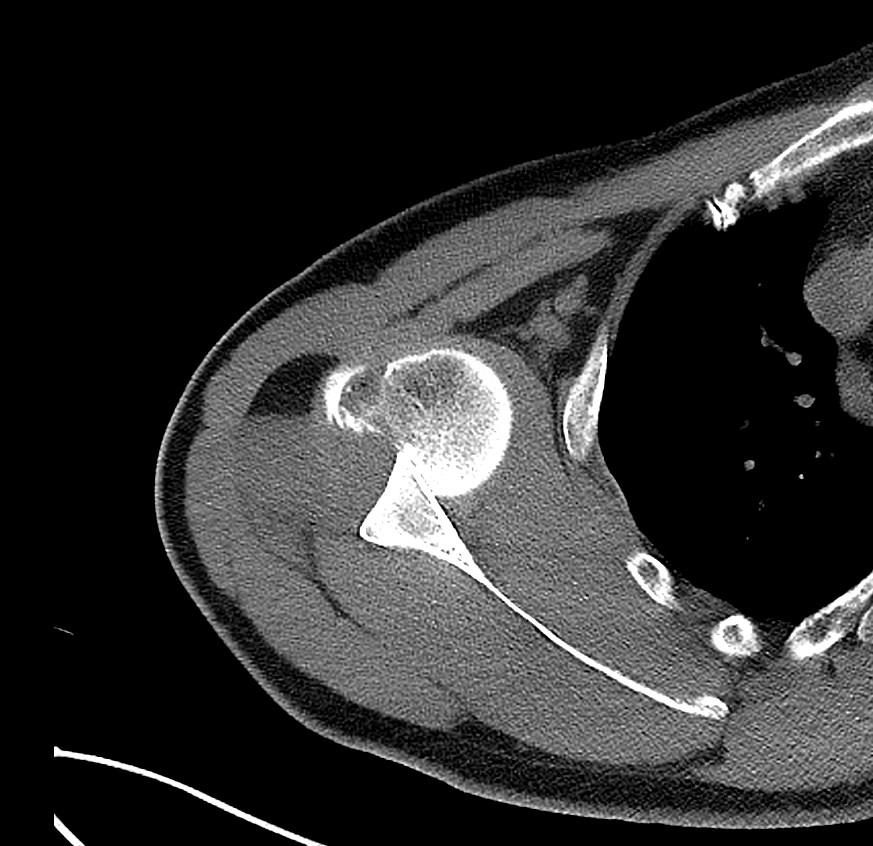

Hydatid disease is a parasitic disease caused by Echinococcosis Granulosus, which may affect the whole body. It most often spreads to the liver and lungs (1,2). Radiological imaging and serological testing are generally used diagnostic techniques. Ultrasonography is the first choice in radiological imaging for the diagnosis of hydatid cyst. However, CT and MRI can be used for differential diagnosis or in classification. Ultrasonography images of hydatid cysts vary according to the stage of maturation (3).

Gharbi classified hydatid cyst ultrasonographic images into 5 types: Type 1, walled, unilocular, anechoic; type 2, separated membranes; type 3, multisepta, daughter vesicles; type 4, heterogenic, hypo-hyperechogenic; type 5, calcification of a section of the wall or completely calcified (4). The cysts characteristically have three components: Pericyst, Exocyst, and Endocyst.